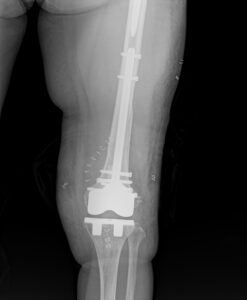

通常であれば、膝関節を開けて逆行性髄内釘挿入手術を行います。

本来はそれほど難易度が高い手術ではありませんが、刺入部に膝人工関節、

固定すべき大腿骨近位に人工股関節があるため、挿入方向や髄内釘のサイズが限られ、

骨折整復が困難となります。

強固な固定が得られたので、激痛のため身じろぎもできなかった状態から、

手術翌日には車椅子に移乗できるようになりました。